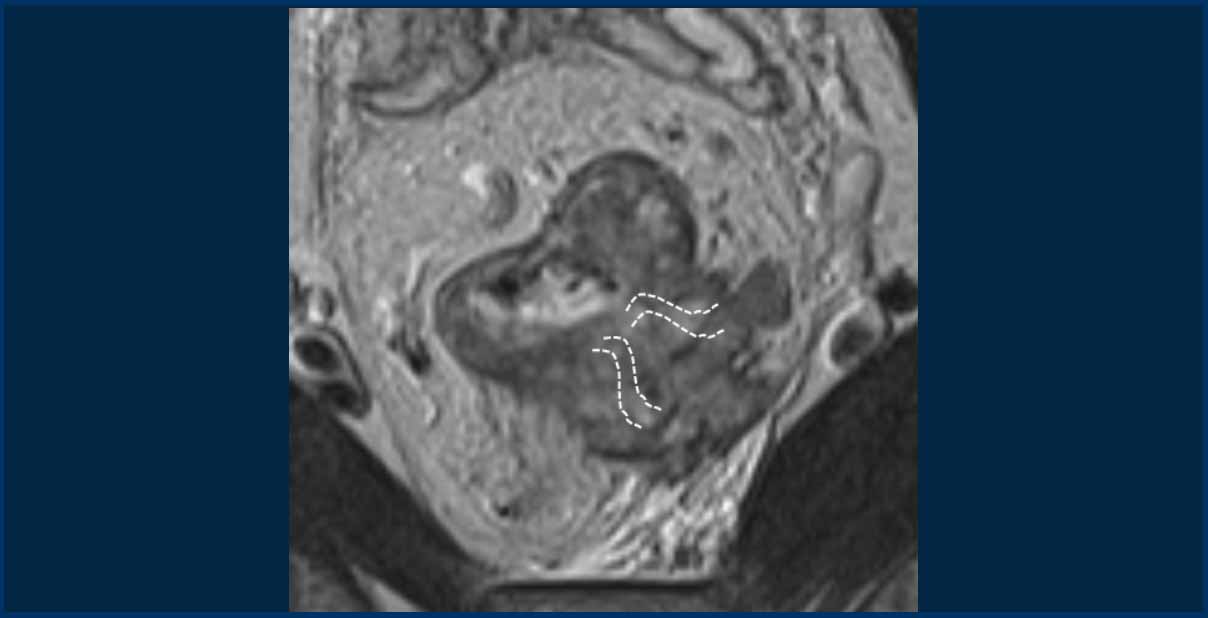

Tumor deposits and EMVI

Tumor deposits are strongly associated with EMVI, often considered a continuation of vascular tumor spread—beginning with EMVI and progressing to tumor deposits in advanced disease [ref]

MRI data show that tumor deposits co-occur with EMVI in up to 80% of cases [ref].

Image Example

• White arrows: EMVI—tumor signal extending into adjacent vessels, with vessel expansion and contour disruption.

• Black circles: Tumor deposits seeded along the vessels.